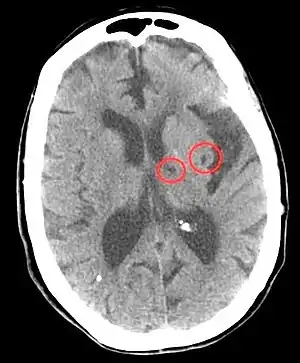

| CT scan of two lacunar strokes. | |

A silent lacunar infarction (SLI) is one type of silent stroke which usually shows no identifiable outward symptoms, and is thus termed "silent." Because stroke is a clinical diagnosis (that is, it is defined by clinical symptoms), there is debate about whether SLI are considered to be strokes, even though the pathophysiology is presumably the same. Individuals who have a SLI are often completely unaware they have had a stroke. This type of stroke often causes lesions in the surrounding brain tissue that are visibly detected via neuroimaging techniques such as MRI and computed axial tomography (CT scan). Silent strokes, including silent lacunar infarctions, have been shown to be much more common than previously thought, with an estimated prevalence rate of eleven million per year in the United States. Approximately 10% of these silent strokes are silent lacunar infarctions. While dubbed "silent" due to the immediate lack of classic stroke symptoms, SLIs can cause damage to the surrounding brain tissue and can affect various aspects of a person's mood, personality, and cognitive functioning. A SLI or any type of silent stroke places an individual at greater risk for future major stroke.[7][8]

In terms of the diagnosis of a stroke of this nature, the following is done:[12]

- CT scan

- MRI

- CT angiogram